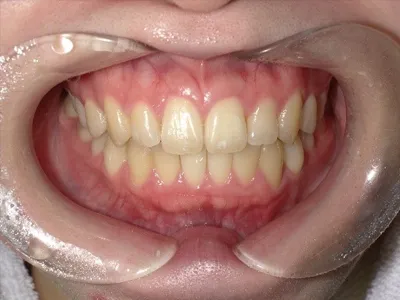

症例3

before

after

| 主訴 | 歯並びきれいにしたい、噛み合わせ良くしたい |

|---|---|

| 治療内容 | マウスピース矯正 |

| 治療期間 | 1年 |

| 費用 | 770,000円(税込) |

| リスク・副作用 | 矯正期間中、歯の移動に伴い、痛み、染みる症状が出ることがあります |